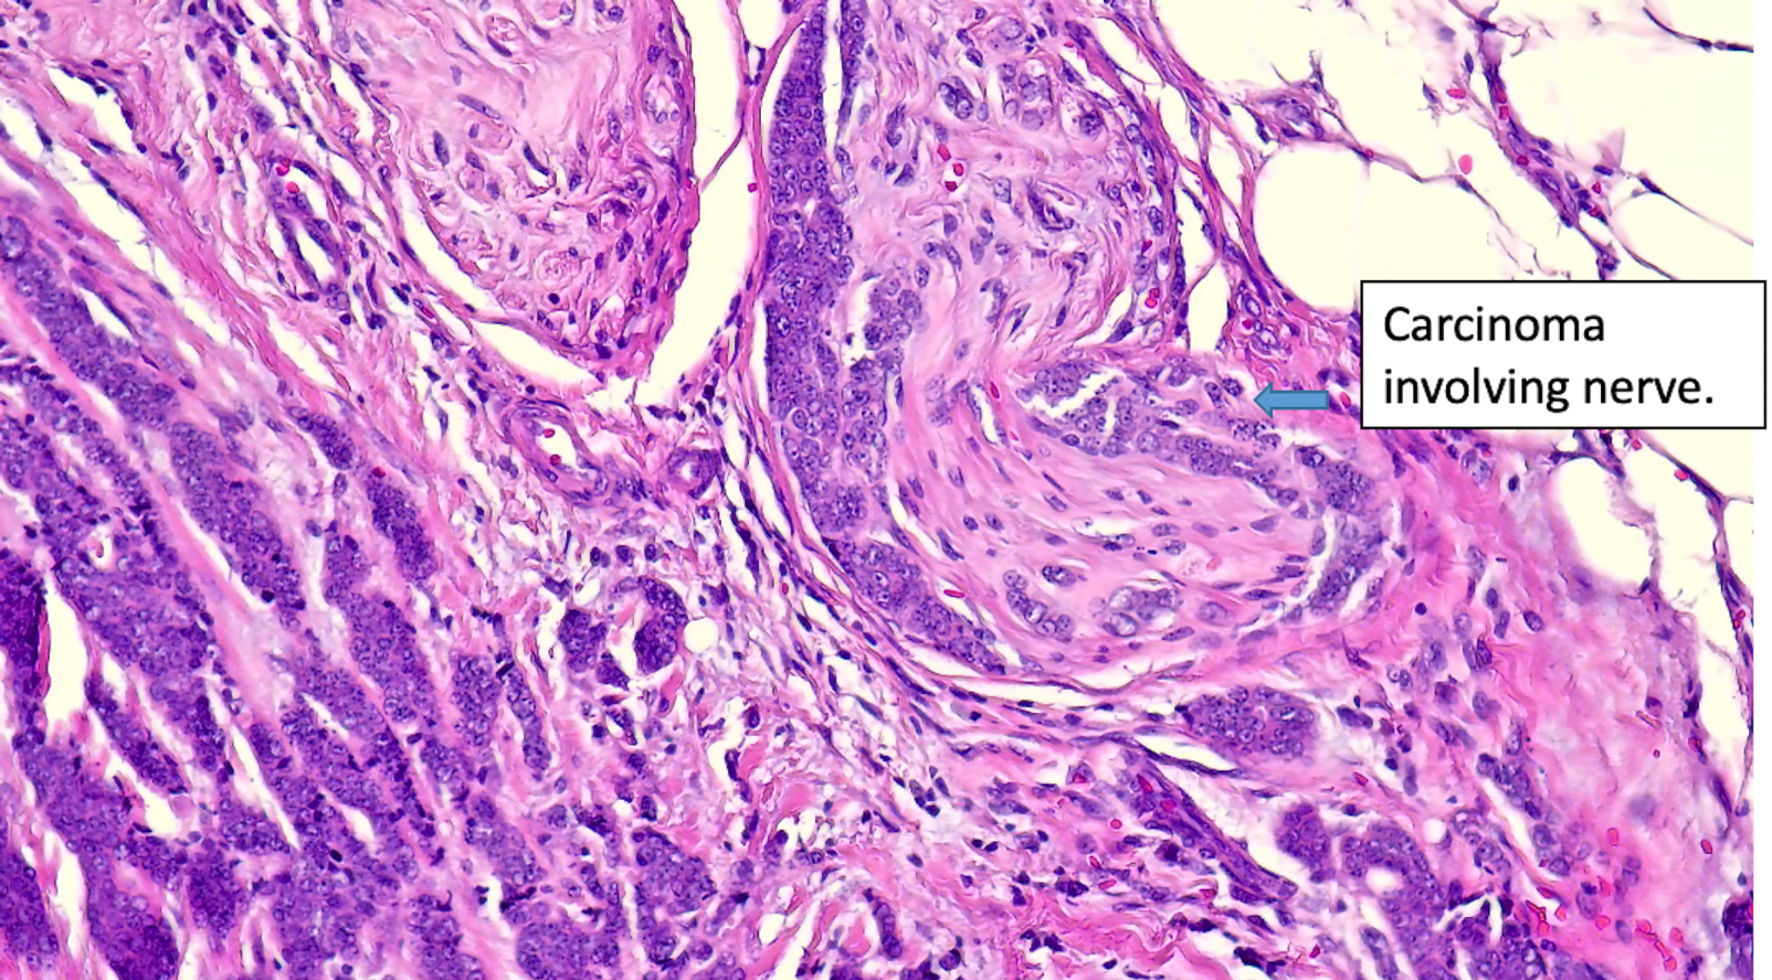

Figure 6. Histologic features of eccrine cell carcinoma at excision. (original magnification × 200).

Click for large image

Figure 7. Histologic features of eccrine cell carcinoma at excision. Extensive perineural invasion. (original magnification × 400).

The patient is a 66-year-old female who presented to our facility in 2024 with a recurrent left lower lip lesion characterized by throbbing pain and numbness. The lesion was initially found in 2017 and later recurred twice in 2020 and 2023, which was managed at another facility. The first surgery was done in 2017 with R0 resection. Pathology report of the recurrent lesion revealed invasive carcinoma, likely ductal carcinoma of the breast with neuroendocrine differentiation. Immunohistochemical stains were positive for CK7, GCDFP-15, mammaglobin, ER (99% strong), PR (99% strong), synaptophysin, and chromogranin, while negative for S100 and p63. E-cadherin showed a strong membranous pattern, suggestive of a ductal phenotype (Figs. 1-7). These findings indicated a primary ductal carcinoma of the breast. However, further investigation revealed no evidence of primary breast cancer. The recurrence of the lesion in 2020 led to another R0 resection, revealing a poorly differentiated carcinoma with potential neuroendocrine and sebaceous differentiation. The patient subsequently developed pain and contractures in the excision area, which prompted her to consult plastic surgery services in 2023, leading to lip reconstruction and another biopsy. This procedure resulted in an R2 resection, with the finding of poorly differentiated adenocarcinoma with extensive perineural invasion evident at the margins. Accessory breast tissue was carefully examined, but no trace of it was found in any of the slides. The pathology slides were originally obtained from the outside facility and reviewed by a dermatopathologist and breast-specialized pathologist. In their interpretation, in the absence of breast lesions, a diagnosis of eccrine carcinoma was considered more appropriate - a known diagnostic pitfall.